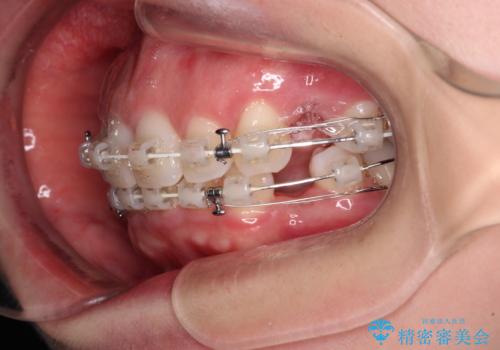

左下の大臼歯2本が顕著に舌側に傾斜しているため、まずは奥歯の咬み合わせを改善をし、その後上下左右の第1小臼歯4本を抜歯することで口元を引っ込めながら整えることとしました。

奥歯の咬み合わせ改善には1年ほどの期間と処置中の噛みにくさを強いることとなりましたが、抜歯後はスムーズに治療を完了させることができました。

歯ぎしりの際に奥歯が干渉していた咬み合わせも理想的な状態に改善できました。